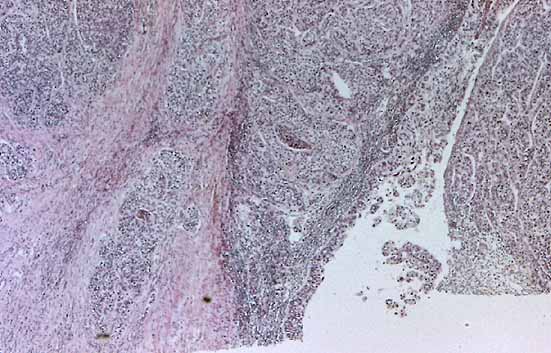

Figura 8.- H-E(10x):Tumoración que surge de la células transicionales de la pelvis renal, las cuales se disponen formendo nidos con áreas de necrosis central e infiltran el parénquima.